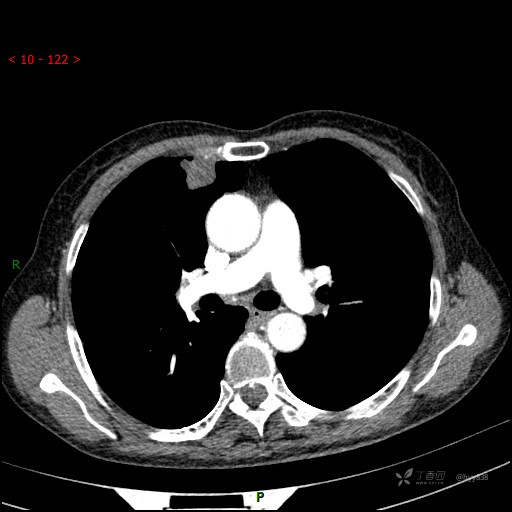

增强动脉期